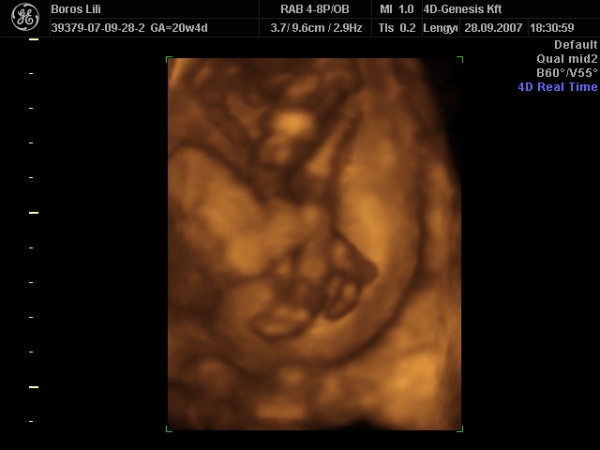

Szerintem nem vagy megőrülve! Ha hiszel ezekben a jelekben, tedd azt. Bár én az els terhességemnél abban voltam, hogy nekem fiam lesz. Aztán a 4d-n úgy széttette a kisasszony a lábait, hogy nem lehetett eltéveszteni. Nem volt egyáltalán rossz érzés, mert én is úgy voltam vele, hogy lényegtelen a neme, csak egészséges legyen.

Majd kb 5 hét múlva kiderül a 4d-s mozin.